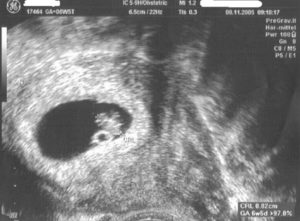

УЗИ — беременность 7 акушерских недель, один плод

Проводя УЗИ на таком раннем сроке, рассмотреть детально малыша вряд ли получится. На мониторе будет виден черный овал, внутри которого и расположен плод. Если хорошо присмотреться, то у будущего малыша можно увидеть очертания головы, туловища и конечностей.

Как правило, в первом триместре проводят трансвагинальное УЗИ. С его помощью можно более детально рассмотреть состояние плода.

Вид эмбриона в 7 недель напоминает форму фасолины, а размеры плода колеблятся в пределах 7-11 мм. На 7 неделе с помощью ультразвуковой диагностики можно услышать сердцебиение плода, определить количество ударов.